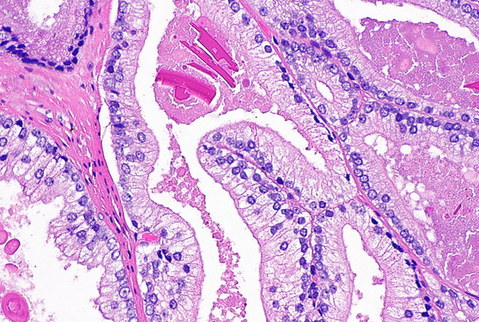

- Modification of grading method for some variantsPseudohyperplastic Adenocarcinoma

Resembles benign hyperplastic glands in terms of architecture but has atypical nuclear features

ISUP recommends grading them as Gleason 3+3= 6

Usually there is loss of basal cell markers and over-expression of AMACR